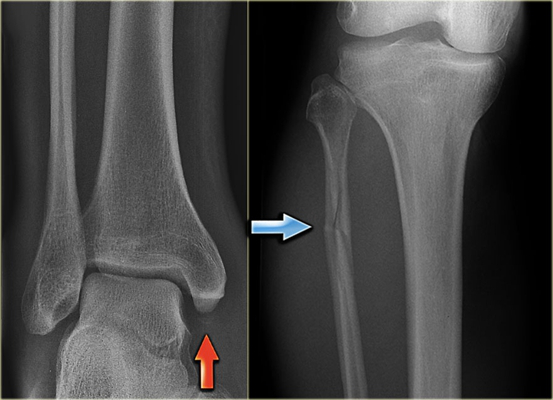

骨折圖片